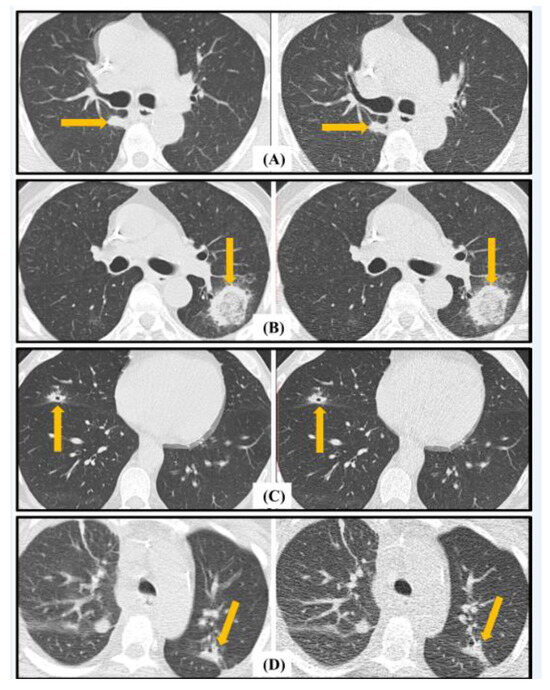

| Major: • Macro nodule. • Halo sign. • Cavitation. • Consolidation. | |

| Minor: • Ground-glass opacity (GGO). • Nodules (4–10 mm), clustered or isolated. |